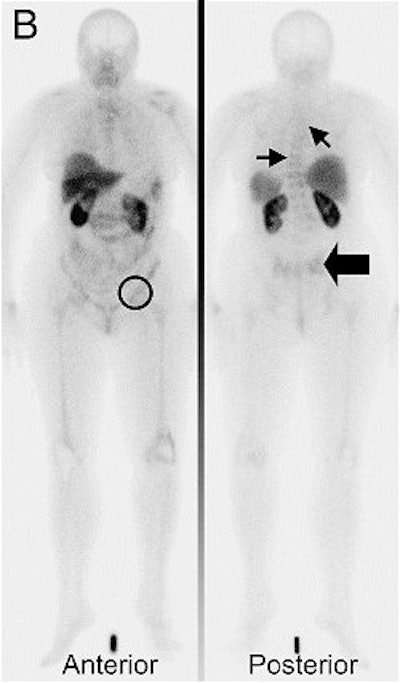

![]() |

| Tc-99m depreotide scintigraphy, assessed before switch to second-line hormonal therapy, was negative. She was a nonresponder and the number of bone lesions increased. Bieke Van Den Bossche, Simon Van Belle, Frederic De Winter, Alberto Signore, and Christophe Van de Wiele. "Early Prediction of Endocrine Therapy Effect in Advanced Breast Cancer Patients Using 99m-Tc-Depreotide Scintigraphy" J Nucl Med 2006; 47;6-13, Figure 3. |